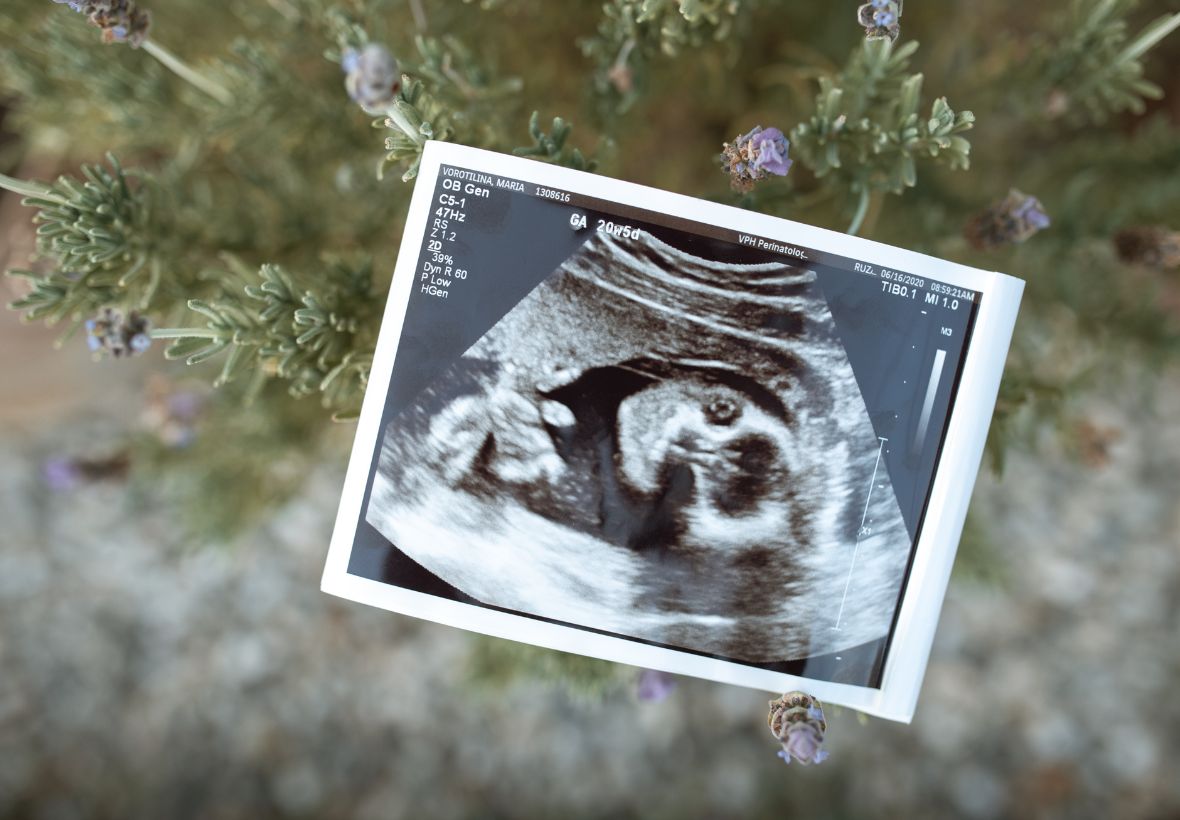

Nuestro equipo realiza un seguimiento personalizado durante todo el embarazo, con consultas periódicas en las que resolvemos dudas, proporcionamos información y cuidamos tanto de tu salud como de la de tu bebé. Además, incluimos orientación nutricional adaptada a tus necesidades y estilo de vida, para favorecer un embarazo saludable y equilibrado.

Las matronas proporcionan cuidados prenatales, educación para el parto, asesoramiento en nutrición y preparación para la lactancia materna. También monitorizan la salud de la madre y el feto, identificando posibles riesgos y orientando en la planificación del nacimiento.